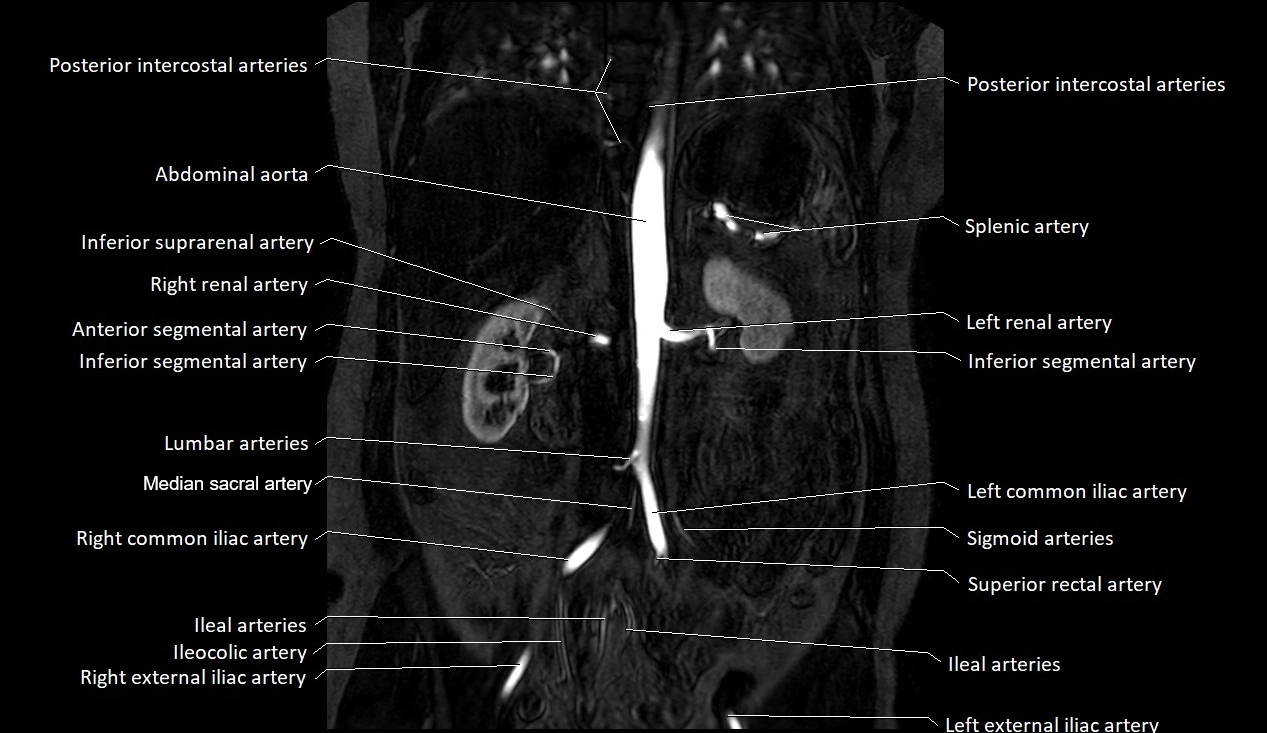

MRI images

image